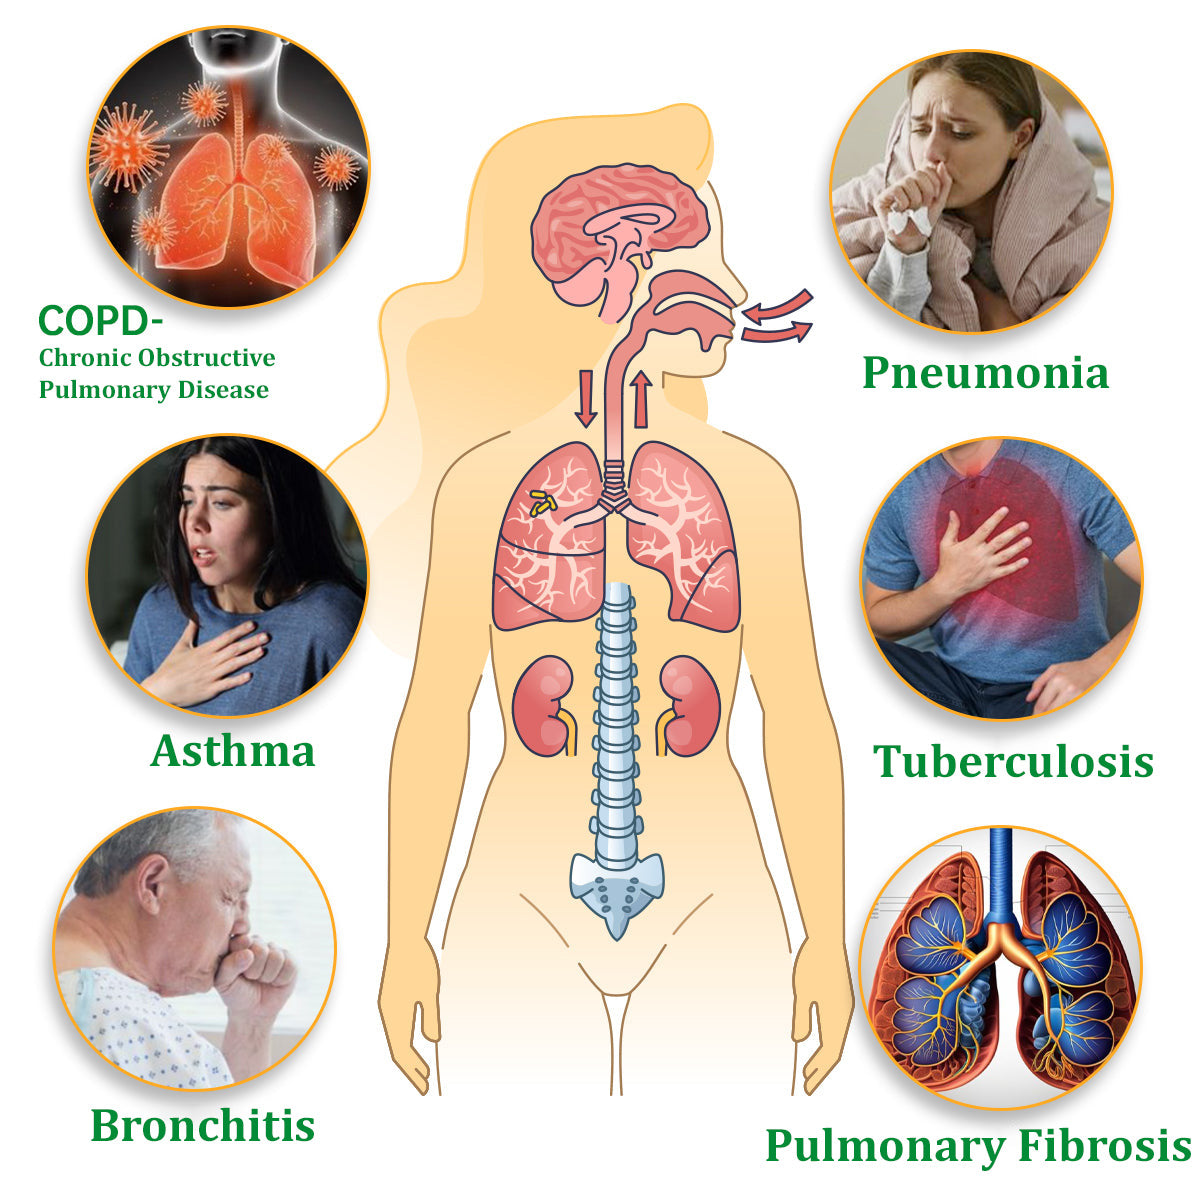

Are you anxious about breathing problems or coughing?

Q3: Can the Breathe Qooes™ Mullein Diffuser help relieve asthma or bronchitis symptoms?

A: Yes, the Breathe Qooes™ Mullein Relaxation Stick’s soothing herbal aroma can help relieve symptoms associated with asthma, bronchitis, and other respiratory discomforts by promoting easier breathing and soothing airway irritation.